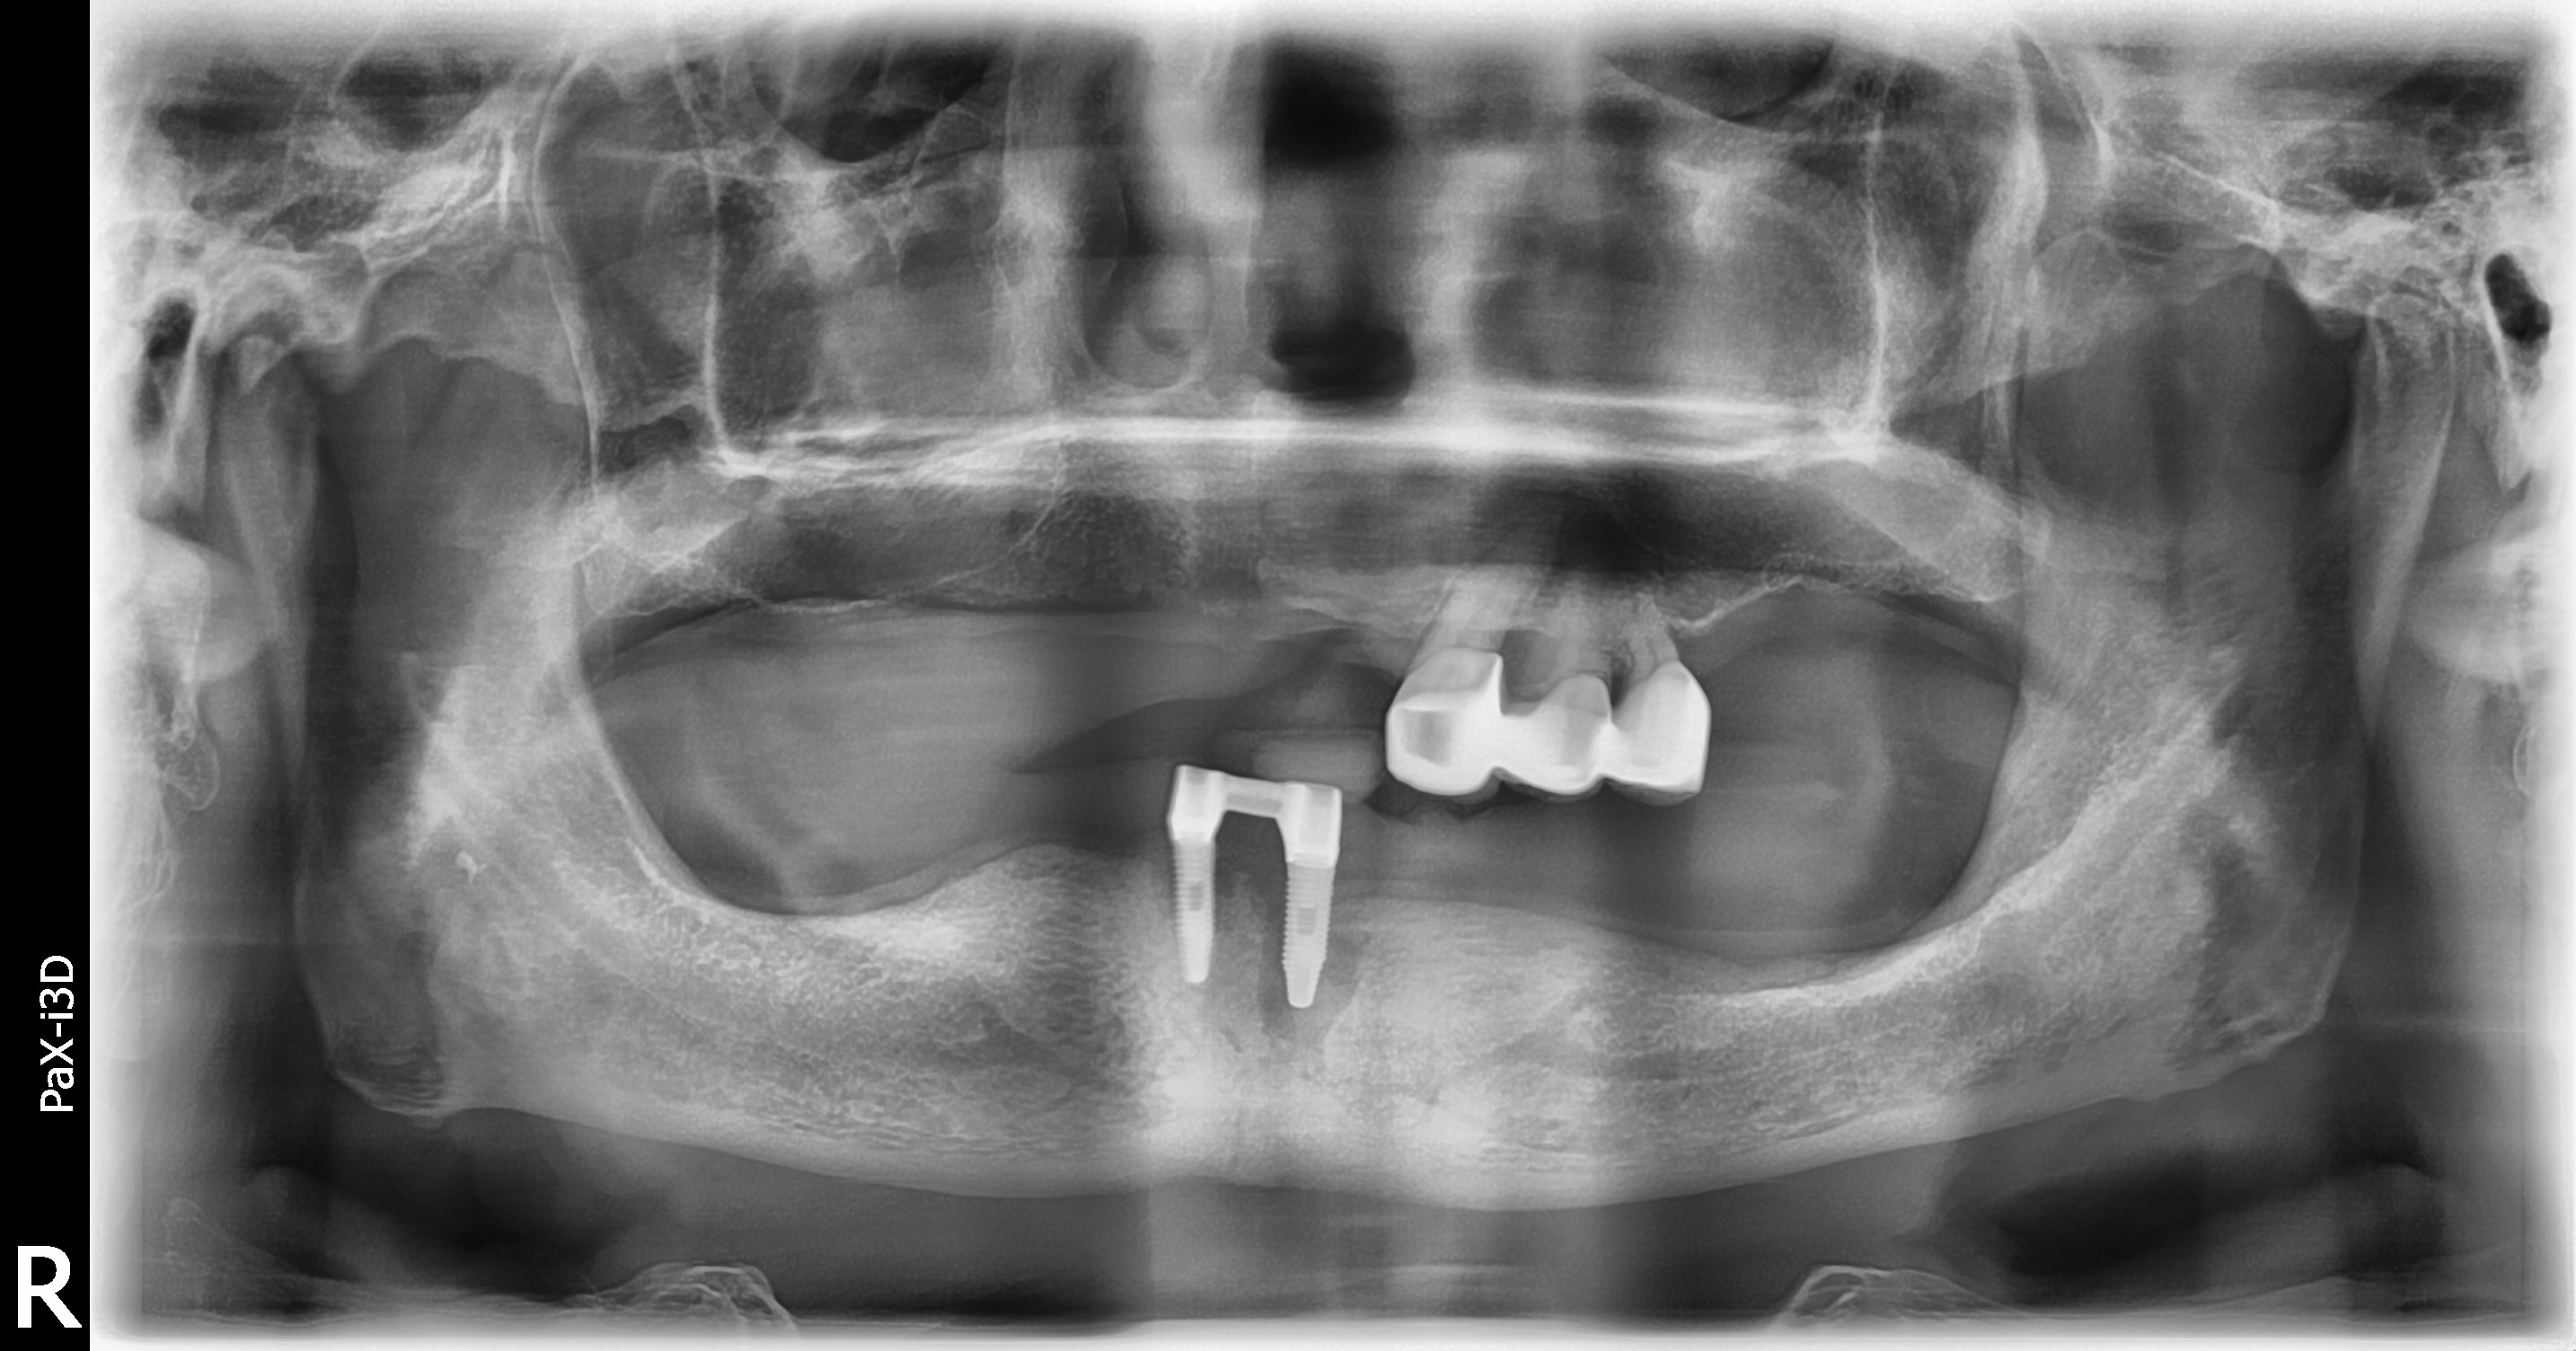

BEFOREAFTERBEFOREAFTER(식립)AFTER(착용)